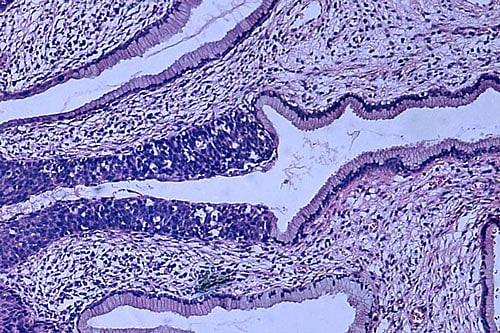

"Cervical cancer incidence declined dramatically in high- income countries after introduction of organised population-based screening programmes using cervical cytology (Pap smear test)," he said.

"However, in India, a national population-based Pap smear screening programme is difficult to implement because of logistic problems related to need for laboratory facilities and expert cytologists."

Visual inspection of the cervix after application of 4 per cent acetic acid (VIA) is a low-cost alternative, he said. However, efficacy of VIA test, conducted by trained health workers, was yet to be ascertained. So Tata Memorial Centre embarked on this research; funds were provided by National Cancer Institute, USA, supplemented by TMC and Women's Cancer Initiative, Mumbai.